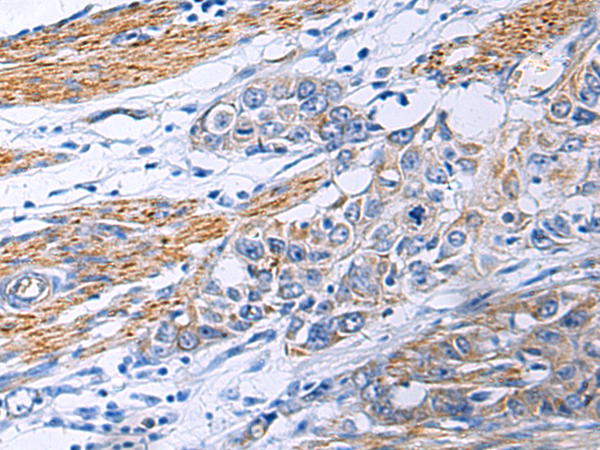

- The image is immunohistochemistry of paraffin-embedded Human colorectal cancer using P13276(POLQ Antibody) at dilution 1/30. (Original magnification: ×200)

- The image is immunohistochemistry of paraffin-embedded Human esophagus cancer using P13276(POLQ Antibody) at dilution 1/30. (Original magnification: ×200)